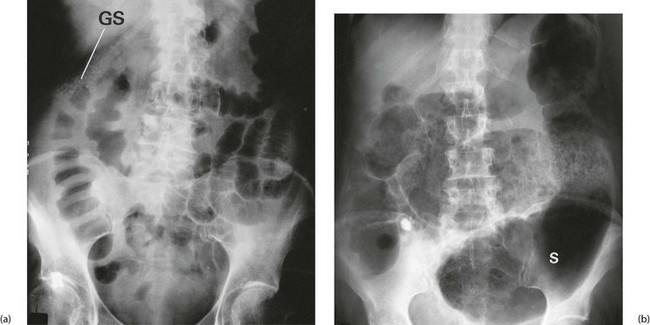

Whatever the cause, patients with acute colitis require urgent hospital admission and resuscitation including fluid, electrolyte and blood replacement. Sigmoidoscopy and biopsy are performed to establish the diagnosis. Stool is sent for microscopy and culture. Plain abdominal radiography is performed to monitor for dilatation, which might indicate toxic megacolon (defined as a colonic diameter greater than 6 cm in the presence of pyrexia or tachycardia). In the absence of megacolon, plain radiography may demonstrate other features of acute ulcerative colitis as shown in Figure 28.5.